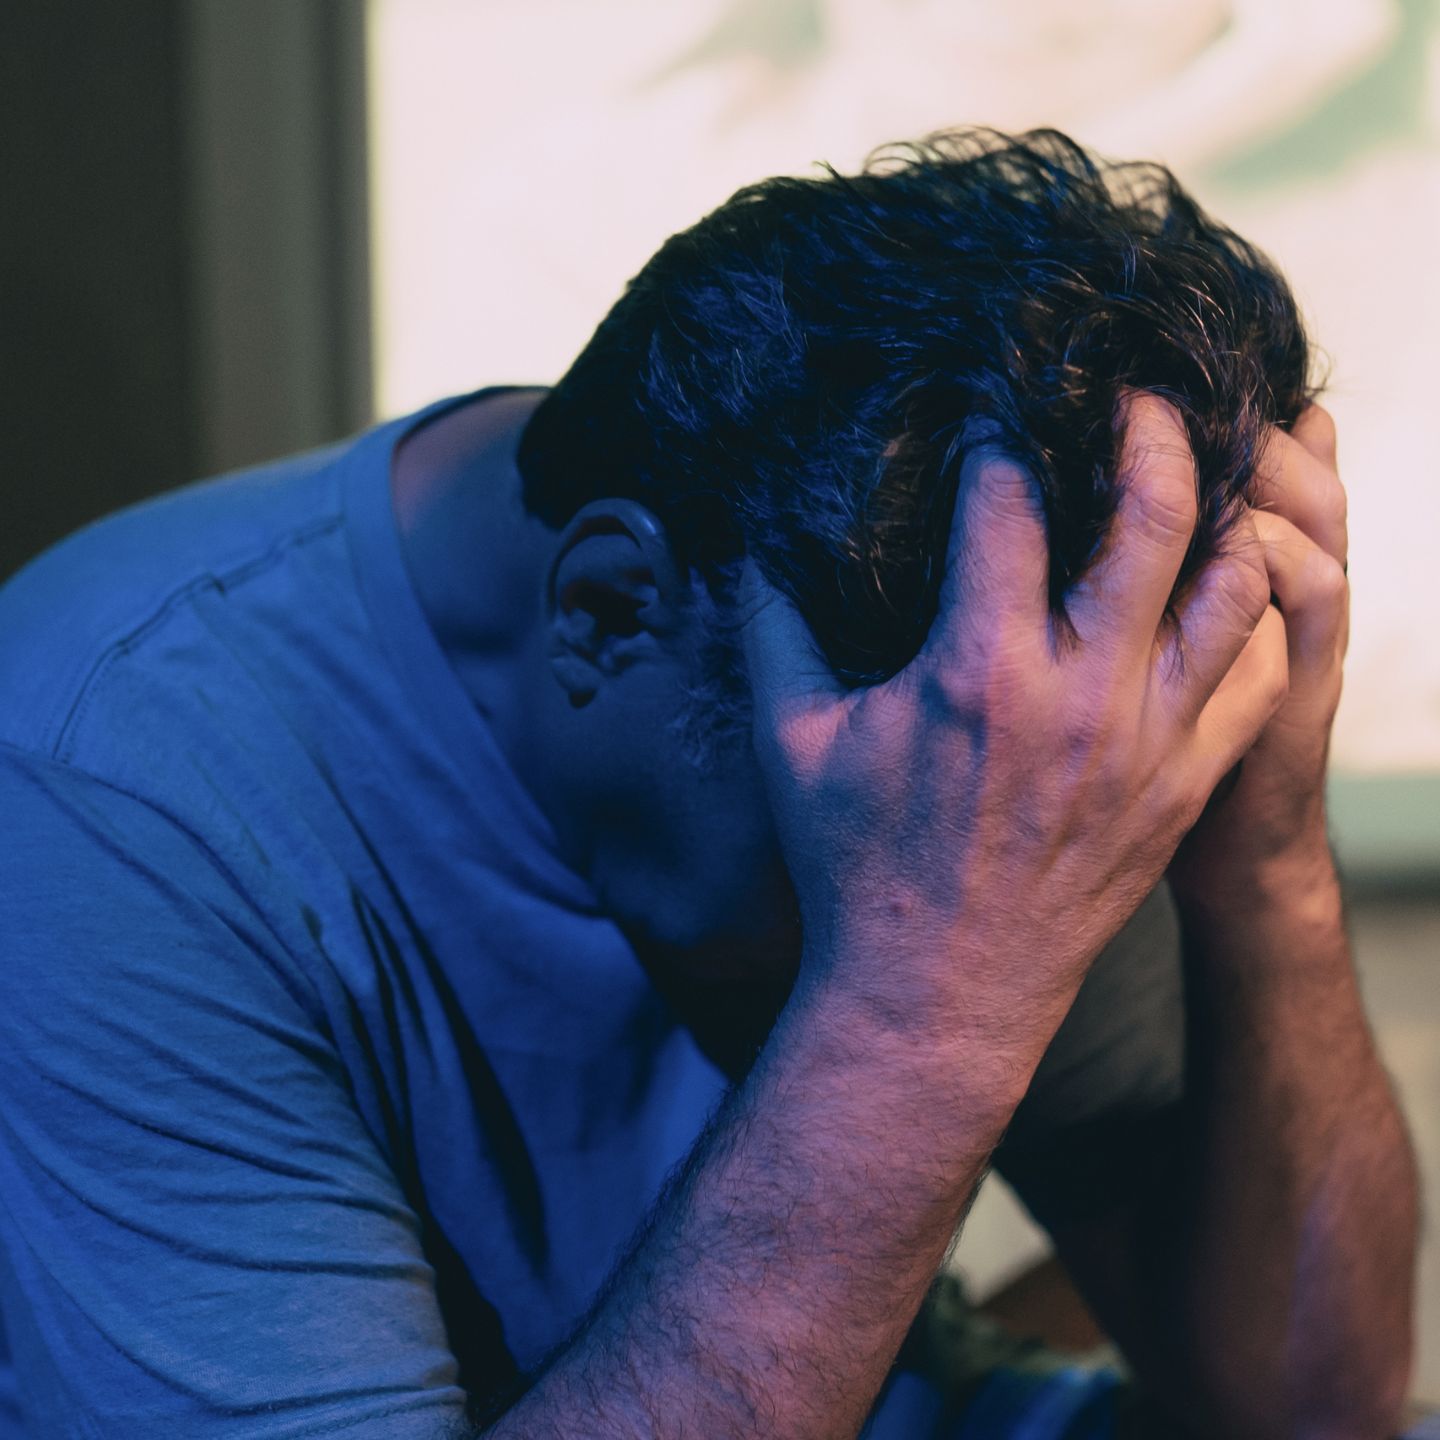

50% des hommes de plus de 40 ans Souffrent de Troubles de L’érection

Les troubles de l’érection sont devenus très répandus, à tel point que passé un certain âge plus de la moitié des hommes en souffrent régulièrement.

Les hommes qui souffrent de difficultés à garder de bonnes érections se trouvent dans des situations inconfortables:

- Difficulté à garder une érection durant plusieurs minutes ou plusieurs heures

- Erection demie-molle

- Problèmes de relation de couple

- Partenaire insatisfaite sexuellement

- Perte de confiance et dépression

- Absence de libido et de désir

Vivre avec des problèmes d’érection peut être extrêmement frustrant et même mener à la dépression dans certains cas, ou au divorce.